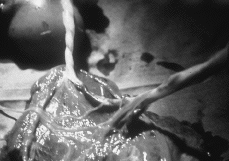

El diagnóstico y seguimiento prenatales son importantes, ya que de ello depende la supervivencia del gemelo perfusor. Se han descrito diagnósticos muy precoces (a las nueve semanas) mediante ecografía transvaginal (9). Mediante ecografía convencional el gemelo acardio puede presentar movimientos espontáneos, tener más o menos desarrolladas las demás estructuras corporales, pero no presenta movimientos cardíacos. El desarrollo corporal depende de la gravedad del proceso y de la precocidad del mismo. Suele desarrollarse mejor la mitad inferior del cuerpo, ya que la sangre llega desde la arterias ilíacas. En la cavidad abdominal suelen verse imágenes econegativas. El 60-75% de los casos son acéfalos (Fig. 2).

| Figura 2.Imagen ecográfica, en corte longitudinal, del gemelo acardio. Se aprecian las imágenes típicas econegativas que ocupan el abdomen fetal y una columna vertebral rudimentaria. |